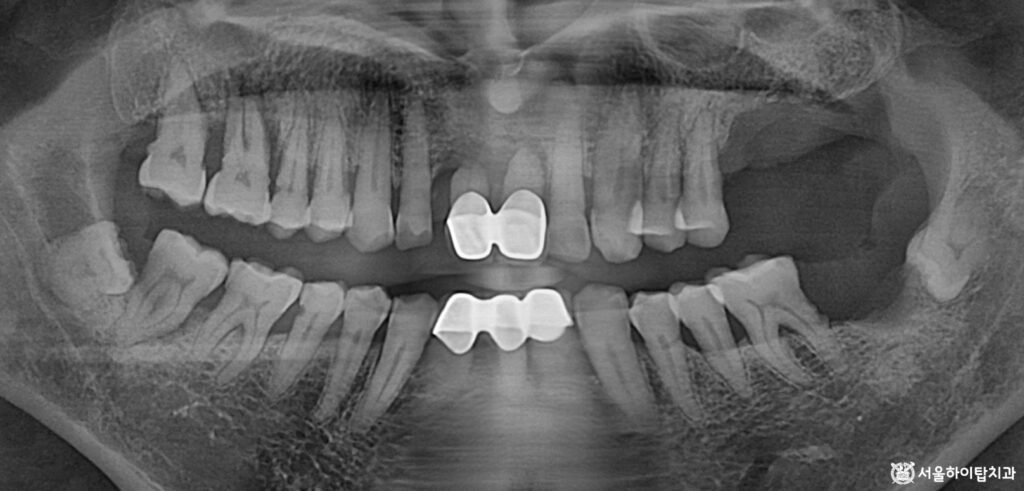

1. 초진

간석역 치과 에서는

한눈에 보더라도 상, 하악 어금니가

상실된 모습을 확인할 수 있습니다.

특히 위턱 부위의 치조골이

상당히 흡수된 모습이 관찰되며,

이는 장기간 기능을 하지 못한 치아

부위에서 흔히 나타나는 변화입니다.

또한 앞니 부위를 다시 살펴보면

크라운이 수복되어 있는 모습을

확인할 수 있습니다.

그러나 치근 길이가 짧아진 상태이며,

주변 치조골의 소실 또한 관찰됩니다.

이런 경우 치아를 지지해 주는

구조가 약해지기 때문에,

치아가 흔들리는 동요도(Mobility)가

상당히 높을 것으로 예상됩니다.

즉, 치주조직의 지지력이

크게 감소한 상태이므로

일상적인 저작력만으로도

흔들리거나 파절, 탈락 위험이

높은 상황이라 할 수 있습니다.